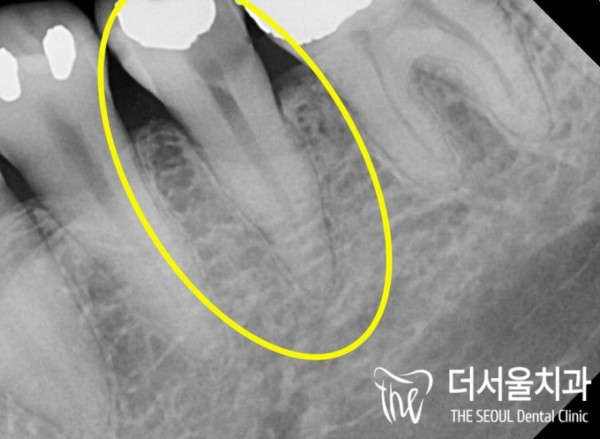

이런경우 보통 임플란트까지 해야 할수도 있지만

이 환자분은 아주 정도가 심각하지는 않았기 때문에

자연치아를 살릴 수 있는 상태였습니다.

즉, 신경치료를 통해 자연치아를 살리기로 하였습니다.

In this case, you may need to get an implant

This patient wasn't very serious

I was able to save my natural teeth.

In other words, we decided to save our natural teeth through nerve treatment.